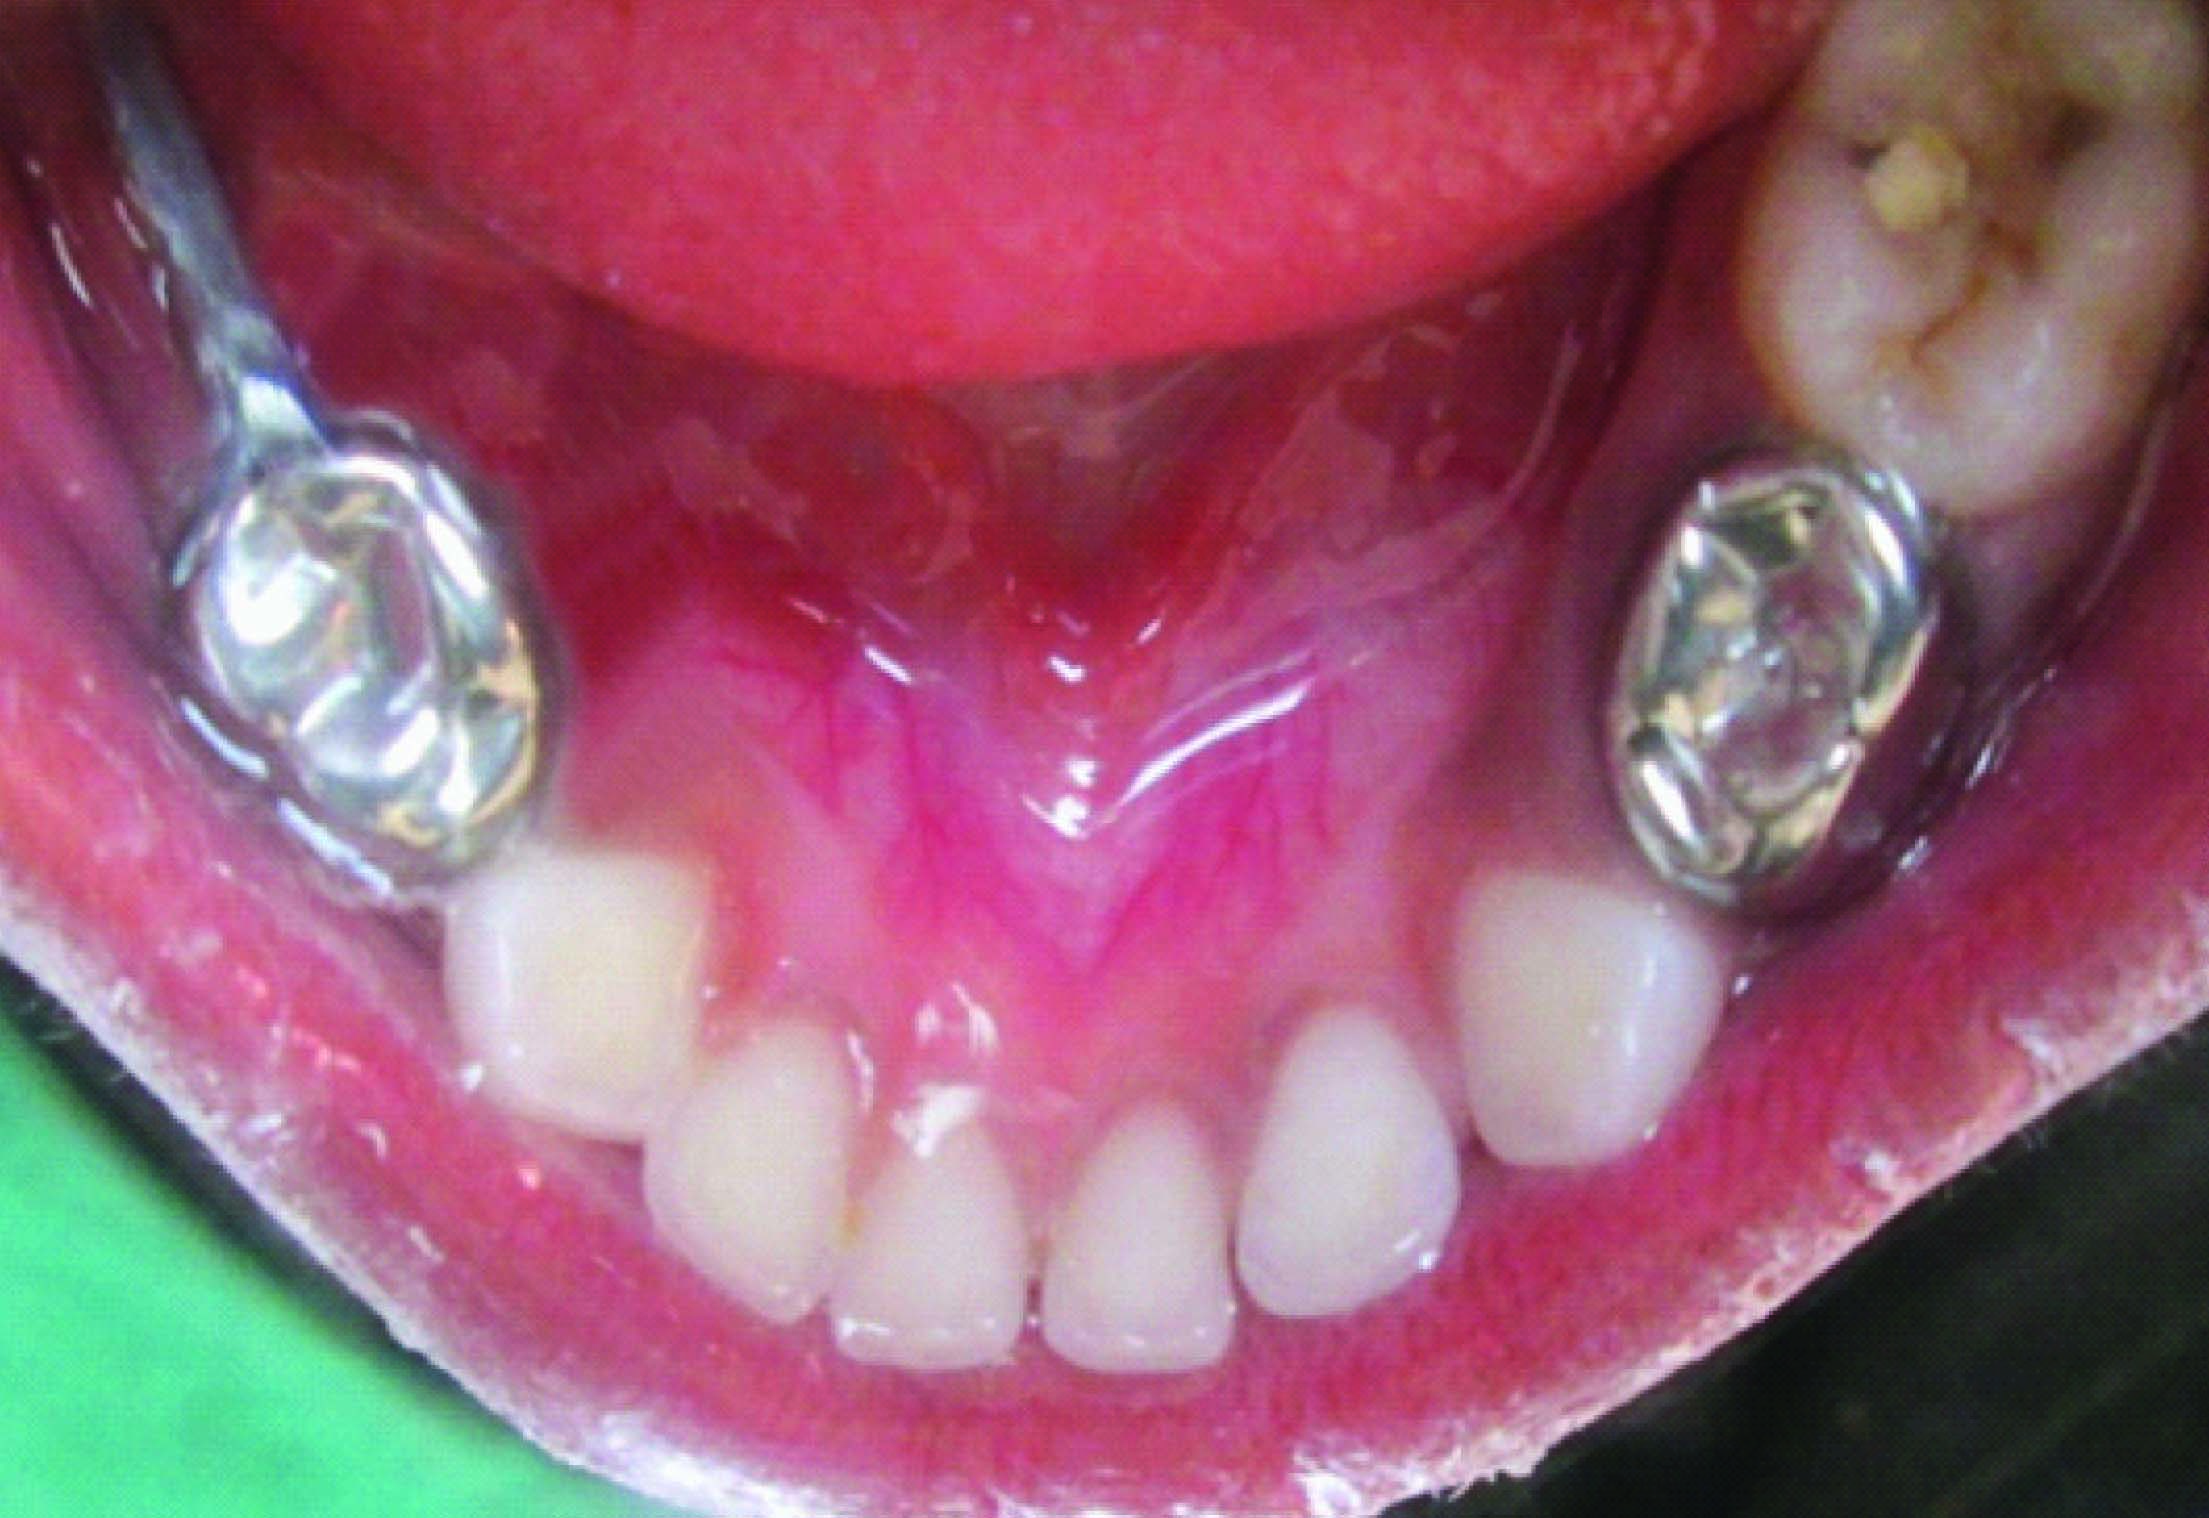

On clinical examination there was deep carious lesion in relation to 74 and 84 and grossly destroyed 64 and 85. Intraoral periapical radiograph of 74 and 84 revealed radiolucency involving pulp and enlarged pulp chamber with short roots suggestive of taurodontism [Table/Fig-1,2]. The teeth were subjected for clinical tests and diagnosis of chronic irreversible pulpitis was made in relation to 64, 74, 84, and 85. The teeth 74 and 84 were treated by multivisit pulpectomy procedure. Obturation was done with vitapex followed by semi permanent restoration with stainless steel crowns [Table/Fig-3].

Extraction followed by space maintainer was planned for 64 and 85 [Table/Fig-4, 5]. On further examination of the patient’s sibling’s similar characteristic radiographic finding of taurodontism was discovered. IOPA of 84, 85 region of brother [Table/Fig-6] and IOPA of 84 region [Table/Fig-7] of sister exhibited taurodontic characteristic. Suspecting this the mother was also subjected to radiographic procedure who to our great surprise exhibited taurodontic appearance of a previously endodontically treated 36 [Table/Fig-8].

Intraoral picture showing stainless steel crown in 74 and distal shoe space maintainer in 84,